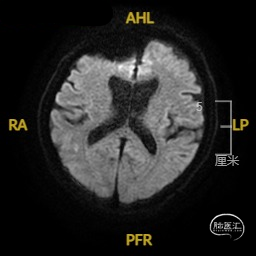

➢ 入院后头核磁检查

患者主因言语不利3天入院,头核磁提示右侧额、顶叶多发低灌注梗塞,脑血管造影提示右侧颈内动脉开口重度狭窄,为责任血管,另外患者前交通动脉、右侧后交通动脉开放不良,并且狭窄严重,考虑到高灌注风险,决定分期处理,一期小球囊扩张改善供血,二期支架成型。